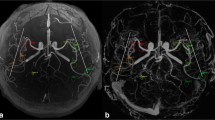

Finally, a 6-year-old boy with a history of arteriovenous malformation presented for follow-up (Fig. 4). Ferumoxytol-enhanced T1 SPGR image indicated an abnormal tangle of vessels in the right occipital lobe. This was subsequently confirmed with DSA. pTOF image generated from 3D ME-GRE prior to ferumoxytol injection highlighted abnormal tangle of vessels in a similar fashion to that of cTOF.

A 6-year old boy with arteriovenous malformation. Ferumoxytol-enhanced (Fe-enhanced) T1 SPGR image shows abnormal tangle of vessels in right occipital lobe (arrowhead), which was subsequently confirmed by DSA (not shown). The pTOF generated from 3D ME-GRE prior to Ferumoyxtol injection shows abnormal tangle of vessels (arrows) similar to cTOF